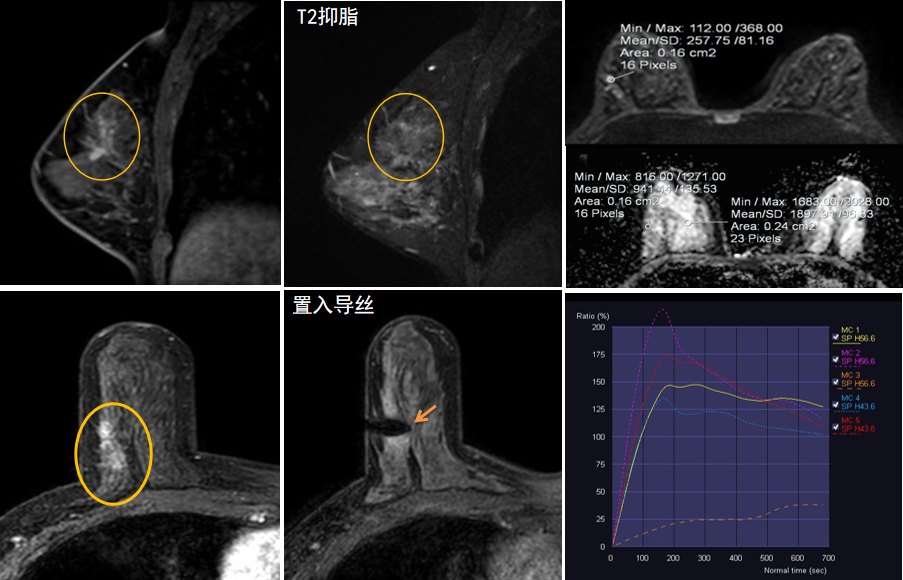

今年45歲的某女士,兩個(gè)月前行超聲檢查發(fā)現(xiàn)右乳結(jié)節(jié),乳腺X線攝影檢查提示右乳外上象限局部腺體結(jié)構(gòu)扭曲并簇狀無定形鈣化,為了進(jìn)一步評(píng)估病變性質(zhì)并確定范圍進(jìn)行了乳腺M(fèi)R平掃 DWI 增強(qiáng)的檢查,經(jīng)MR評(píng)估發(fā)現(xiàn)右乳病變范圍較廣,評(píng)估為BI-RADS 4類可疑病變,需要取得病理學(xué)結(jié)果。

陳寶瑩主任及其帶領(lǐng)的MR介入診療小組詳細(xì)詢問了病情,分析了患者資料,并與患者和臨床醫(yī)生進(jìn)行了充分溝通,確定于手術(shù)前為患者實(shí)施MR引導(dǎo)下的病變穿刺導(dǎo)絲定位和體表范圍確定。手術(shù)前陳寶瑩主任帶領(lǐng)聶品醫(yī)師、馬小偉技師、韓愛萍護(hù)士長等MR介入診療小組成員,借助MR高清的圖像顯示和定位系統(tǒng),確定病變范圍,精準(zhǔn)穿刺置入定位導(dǎo)絲,并準(zhǔn)確標(biāo)記出病變體表范圍,整個(gè)過程患者無任何不適。在定位導(dǎo)絲和體表范圍標(biāo)記的輔助下,甲乳外科劉曉敏主任精準(zhǔn)切除了病變,解除了患者的后顧之憂。

國內(nèi)外指南均建議40歲以上的女性每年行一次雙乳X線攝影(鉬靶)檢查,以篩查乳腺癌。對(duì)于乳腺癌高危人群40歲以前即建議開始乳腺癌篩查,除了進(jìn)行乳腺X線攝影(鉬靶)篩查外需要補(bǔ)充MR檢查,MR檢查敏感性最高,能夠發(fā)現(xiàn)大量X線攝影和超聲檢查陰性的可疑病變,基于多模態(tài)、多參數(shù)的結(jié)構(gòu)和功能成像的基礎(chǔ)上,MR能夠精準(zhǔn)顯示病變位置、范圍以及病變內(nèi)的活性區(qū)域,MR引導(dǎo)下的介入診療不但解決了僅在MR顯示的病變的處置難題,而且能夠精準(zhǔn)定位活性區(qū)域,保證了定位、活檢及旋切的準(zhǔn)確性。